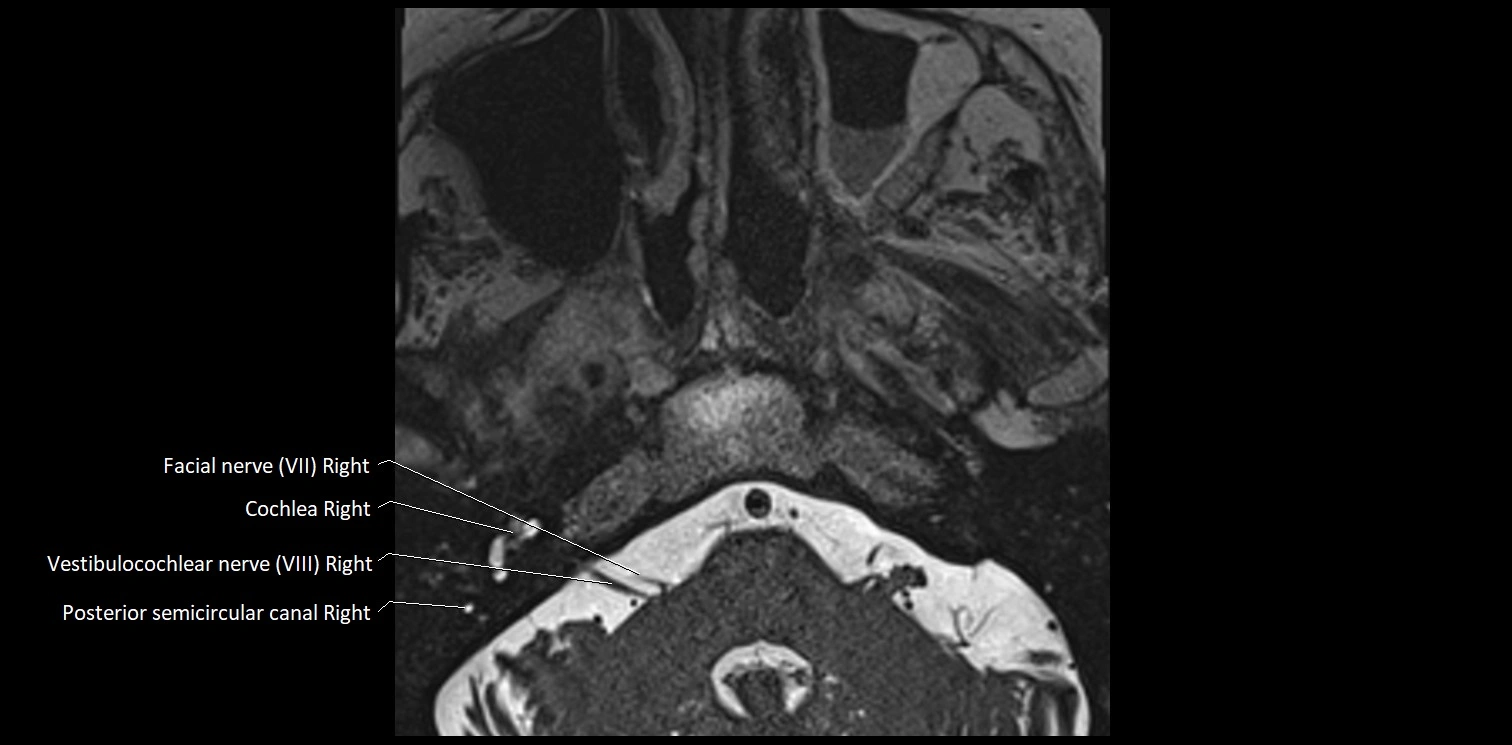

MRI Appearance

• The abducens nerve is a small, thin, linear structure

• Best visualized on high-resolution T2-weighted 3D MRI sequences (e.g., FIESTA or CISS)

• Seen as a hypointense (dark) line running from the brainstem at the pontomedullary junction, traversing the prepontine cistern, and entering Dorello’s canal under the petrosphenoidal ligament, then into the cavernous sinus, and finally the orbit

• May be challenging to visualize in standard MRI due to its small size

• Pathology may be inferred by absence, displacement, or enhancement of the nerve

MRI images

image